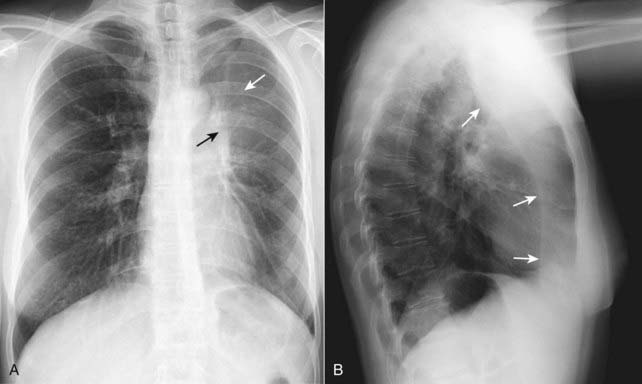

Figure 5-2 Right upper lobe atelectasis.

A fan-shaped area of increased density is seen on the frontal projection (A) representing the airless right upper lobe. The minor fissure is displaced upward (solid white arrow). The trachea is shifted to the right (solid black arrow). The lateral (B) demonstrates a similar wedge-shaped density near the apex of the lung. The minor fissure (solid white arrow) is pulled upward and the major fissure is pulled forward (solid black arrow). This is a child who had asthma leading to formation of a mucous plug, which obstructed the right upper lobe bronchus.

image Right upper lobe atelectasis (see Fig. 5-2)

On the frontal radiograph:

There is an upward shift of the minor fissure.

There is a rightward shift of the trachea.

On the lateral radiograph:

There is an upward shift of the minor fissure and a forward shift of the major fissure.

If right upper lobe atelectasis is produced by a large enough mass in the right hilum, the combination of the hilar mass and the upward shift of the minor fissure produces a characteristic appearance on the frontal radiograph named the S sign of Golden (Fig. 5-11).